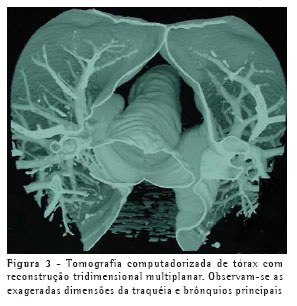

Poucos dias após o término do curso do tratamento com eritromicina, entretanto, o paciente voltou a apresentar tosse produtiva, associada a febre, e o radiograma não evidenciou melhora das consolidações. Foi novamente internado e realizou-se bacterioscopia de escarro, que evidenciou inúmeros polimorfonucleares e cocos gram-positivos em abundância. Cultura não era disponível. Iniciou tratamento com oxacilina intravenosa, obtendo resposta clínica satisfatória em poucos dias, motivo pelo qual foi iniciada a administração de cefalexina por via oral. Voltou a apresentar febre após 48h de uso de cefalexina via oral, o que motivou retorno para tratamento intravenoso e transferência para hospital de maior complexidade para investigação etiológica mais elaborada. O novo exame bacterioscópico de escarro neste momento evidenciou flora polimicrobiana e o paciente iniciou o uso de ceftriaxona associada a amicacina, com duração total de quatro semanas de tratamento, até a total resolução dos sintomas. Neste momento, foi realizada uma tomografia computadorizada de tórax, que demonstrou persistência das lesões consolidativas, de menor tamanho, em ambos os lobos inferiores, e confirmou o alargamento anormal da traquéia e brônquios principais (Figuras 1, 2 e 3), com bronquiectasias cilíndricas bilaterais nos lobos inferiores, caracterizando o diagnóstico de traqueobroncomegalia congênita, ou síndrome de Mounier-Kühn. As provas de função pulmonar evidenciaram aumento da capacidade pulmonar total (123% do previsto) e do volume residual (160% do previsto), sem outras alterações.

O diagnóstico pode geralmente ser feito utilizando-se apenas dados provenientes da radiologia convencional de tórax, através da mensuração do diâmetro traqueal, melhor visualizado na projeção em perfil. A tomografia computadorizada de tórax, entretanto, torna mais precisa essa mensuração. Os limites são 3 cm para diâmetro transverso da traquéia, e 2,4 cm e 2,3 cm para os diâmetros transversos dos brônquios principais direito e esquerdo, respectivamente. As provas de função pulmonar demonstram tipicamente aumento da capacidade pulmonar total à custa do volume residual, eventualmente com sinais de distúrbio ventilatório obstrutivo. Inexistem atualmente tratamentos específicos para esta condição além de antibioticoterapia durante as exacerbações e fisioterapia visando a auxiliar a eliminação de secreções, se houver. A utilização de próteses definitivas é reservada apenas para casos avançados selecionados, pois não existem indicações precisas.(5-6)